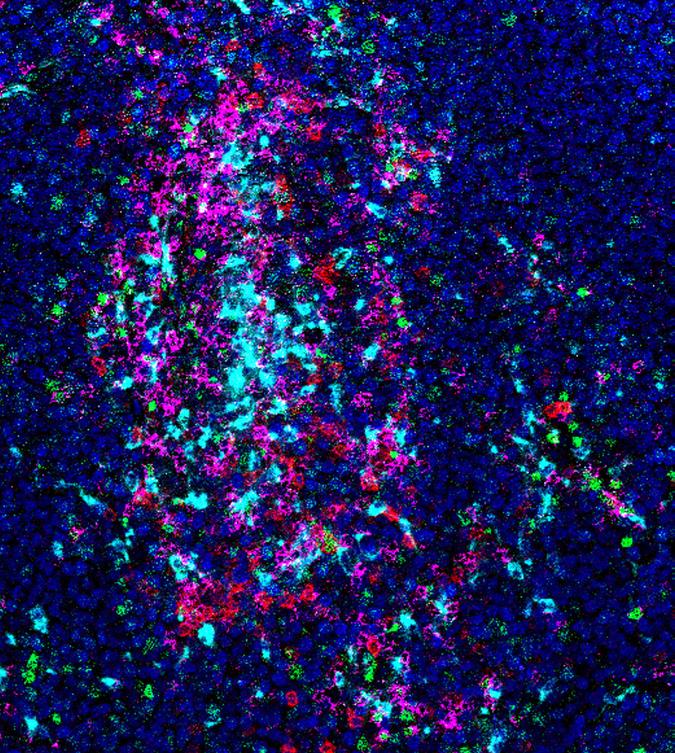

PIVOTAL PROMOTION FOR MEDULLOBLASTOMA RESEARCHER

We are delighted to share that Dr Sara Badodi has been promoted to Junior Principal Investigator (PI) – a pivotal step in her research career.

Dr Badodi joined the team at our Centre of Excellence at Queen Mary University of London, led by Professor Silvia Marino, in 2019, following a generous donation from Peter and Jane Gardiner, who lost their son Ollie to a medulloblastoma, aged 13. She has flourished under Prof Marino’s mentorship and is now setting up her own research group within the Centre with a focus on aggressive medulloblastoma.

Her work will be focused on studying the mechanisms that regulate the activities of proteins which modify the genetic code (DNA) and understanding how these events are involved in the development and maintenance of paediatric brain tumours to identify ways to treat them in a more effective and less toxic way.

Her promotion to Junior PI is a step towards increasing capacity in the UK brain tumour sector and getting us closer to a cure.

Dr Badodi said: “The support from Brain Tumour Research and from Ollie’s family allowed me to continue a research career in the brain tumour field, one of the most challenging scientific areas of research. Thanks to this funding I was able to publish groundbreaking results in medulloblastoma and collect compelling data that allowed me to design the project that I will now develop as a Junior PI.”

Dr Badodi in the lab Medulloblastoma; the most common, high-grade paediatric brain tumour